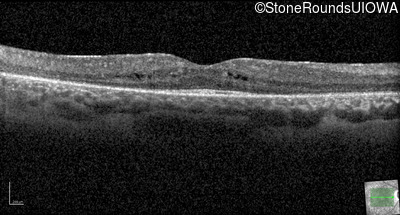

Optical Coherence Tomography - Left - 20/40 -1

Exemplar / OCT Stack